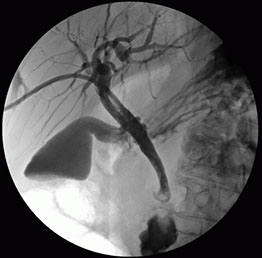

Estenosis Vías Biliares

Una estenosis de las vías biliares a menudo es causada por una lesión en lasvías biliares durante una cirugía. Por ejemplo, puede ocurrir después de una cirugía para extirpar la vesícula biliar. Otras causas de esta afección pueden ser: Cáncer de las vías biliares, hígado o páncreas.

Un stent (endoprótesis) es un pequeño tubo de metal o plástico tubo que se coloca a través de la obstrucción en el conducto. Este pequeño tubo mantiene el conducto abierto para permitir la descarga de bilis al intestino delgado.